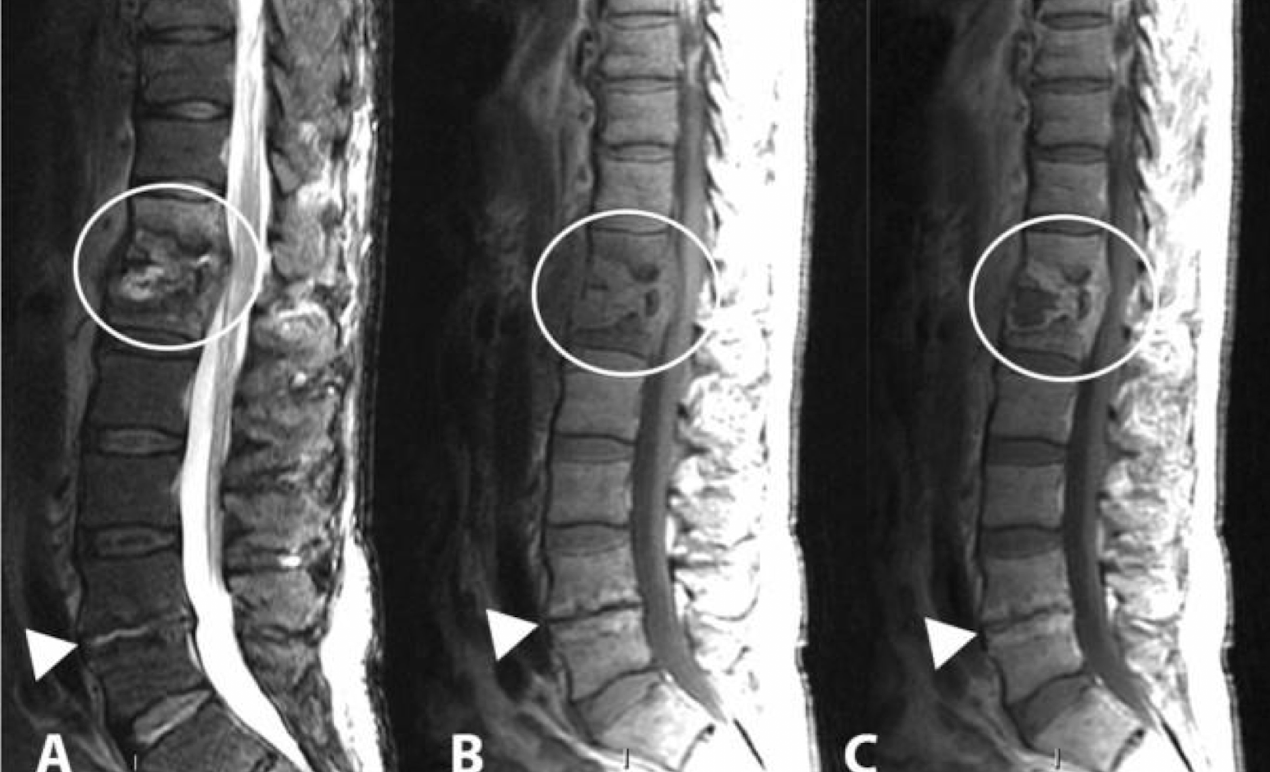

RM

LO MEJOR

Edema de medula

colección hipo en T1 hiper T2

capta contraste periférico

permite distinguir de proceso degeerativo

permite valorar extensión a estructuras adyaventes: psoas y médula